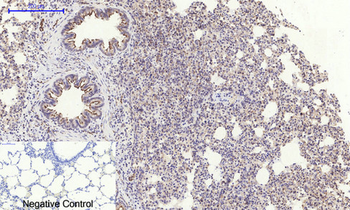

Immunohistochemical analysis of paraffin embedded Human astroglioma tissue labeling Tau with orb1294394 at 1/300.

Immunohistochemical analysis of paraffin embedded Human brain tissue labeling Tau with orb1294394 at 1/200.

Immunohistochemical analysis of paraffin embedded mouse Alzheimer’s tissue labeling Tau with orb1294394 at 1/1000 RT 1hr. Epitope Retrieval methods: Citrate Buffer, pH 6.0.